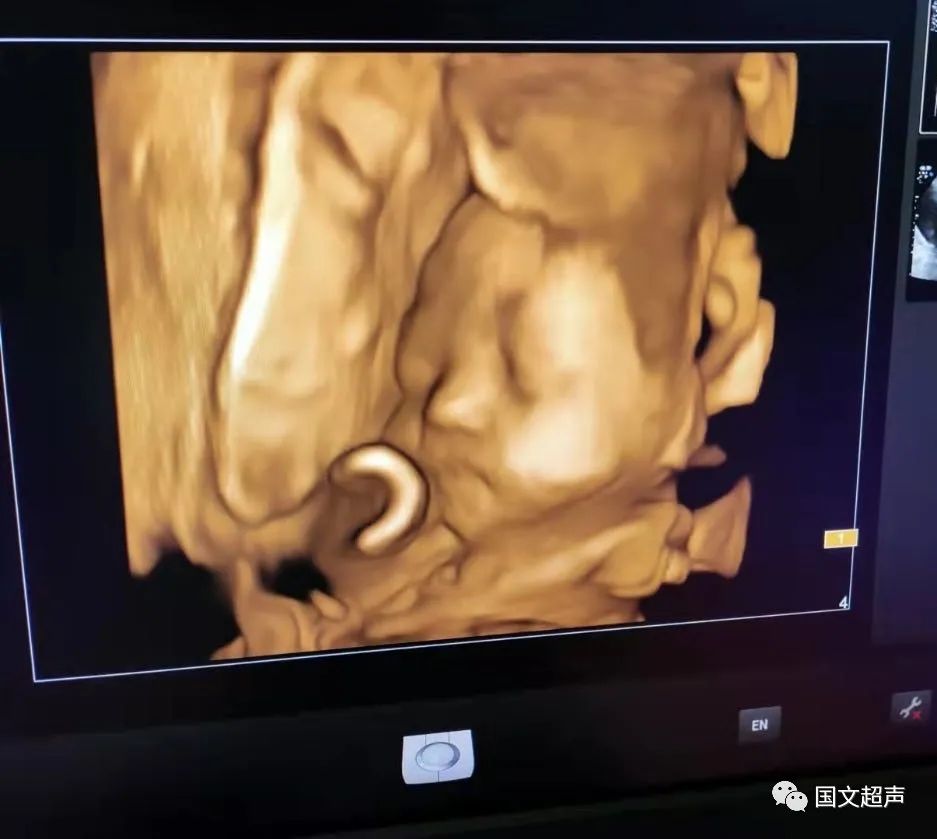

一.飛利浦EPIQ7高端四維彩超

我院目前使用的是飛利浦EPIQ7高端四維彩超,它擁有高品質(zhì)自動成像分析技術(shù),分辨率及清晰度高,可以較清晰的顯示宮內(nèi)胎兒的生長發(fā)育情況,為診斷胎兒先天性畸形,如唇裂、脊柱裂、顱腦發(fā)育異常、骨骼發(fā)育異常、心血管畸形等提供準(zhǔn)確的科學(xué)依據(jù)。